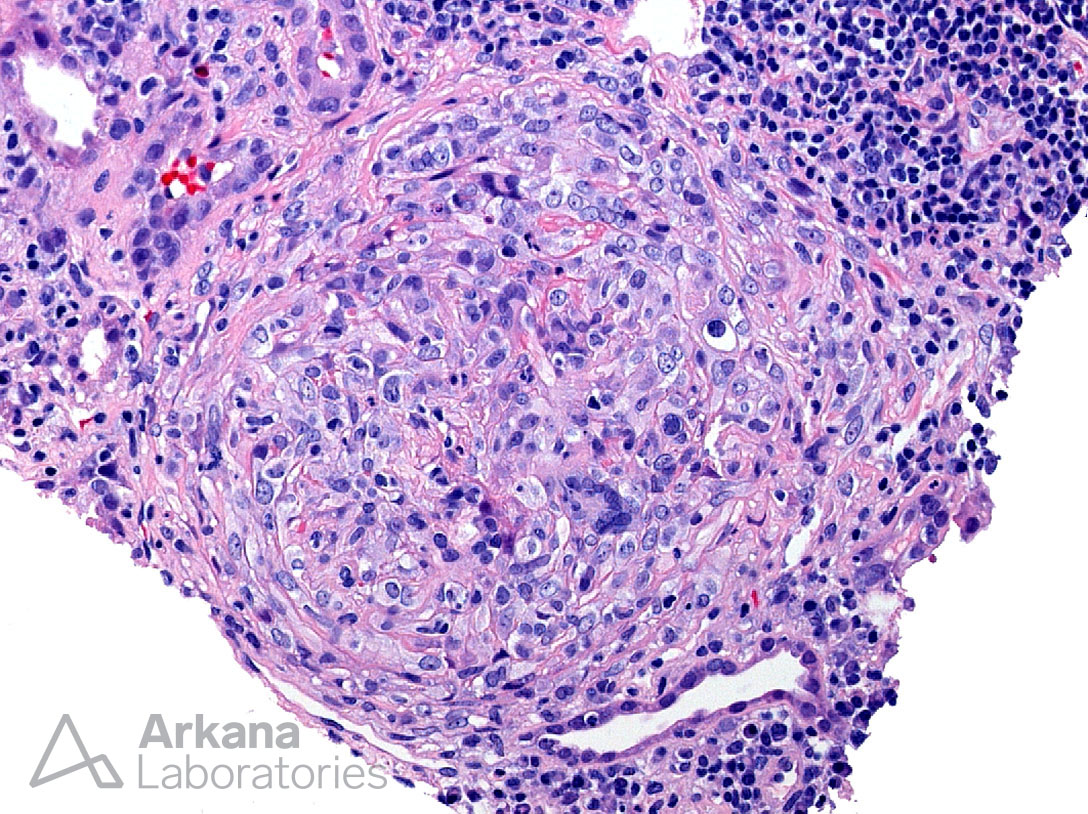

Giant Cells in Crescent in Anti-GBM Disease, H&E Stain